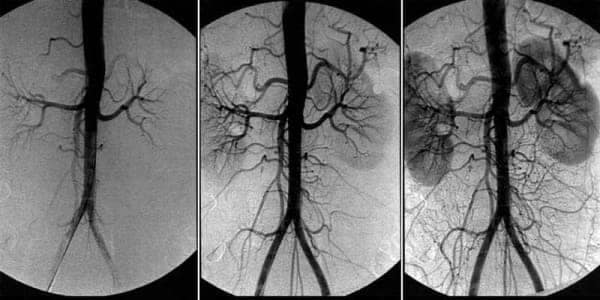

За первый месяц Cardiodoc очистит ваши сосуды примерно на 70%. Удалит до 2 кг холестериновых бляшек, до 1 кг тромбов и 400 г кальциевой извести.

За 2,5 месяца приема Cardiodoc кровообращение восстанавливается на 99,71%.

Кровообращение восстанавливается системно — во всех сосудах, артериях и капиллярах.

6. Нормализация работы сердца

Очищение аорты благотворно влияет на тонус сердечной мышцы. В 93%

случаев проходит тахикардия, в 99% — ишемия.

-

Нормализуется сердечный ритм и пульс.

- Проходят боли в

сердце.

- В 17 раз снижается риск инфаркта!